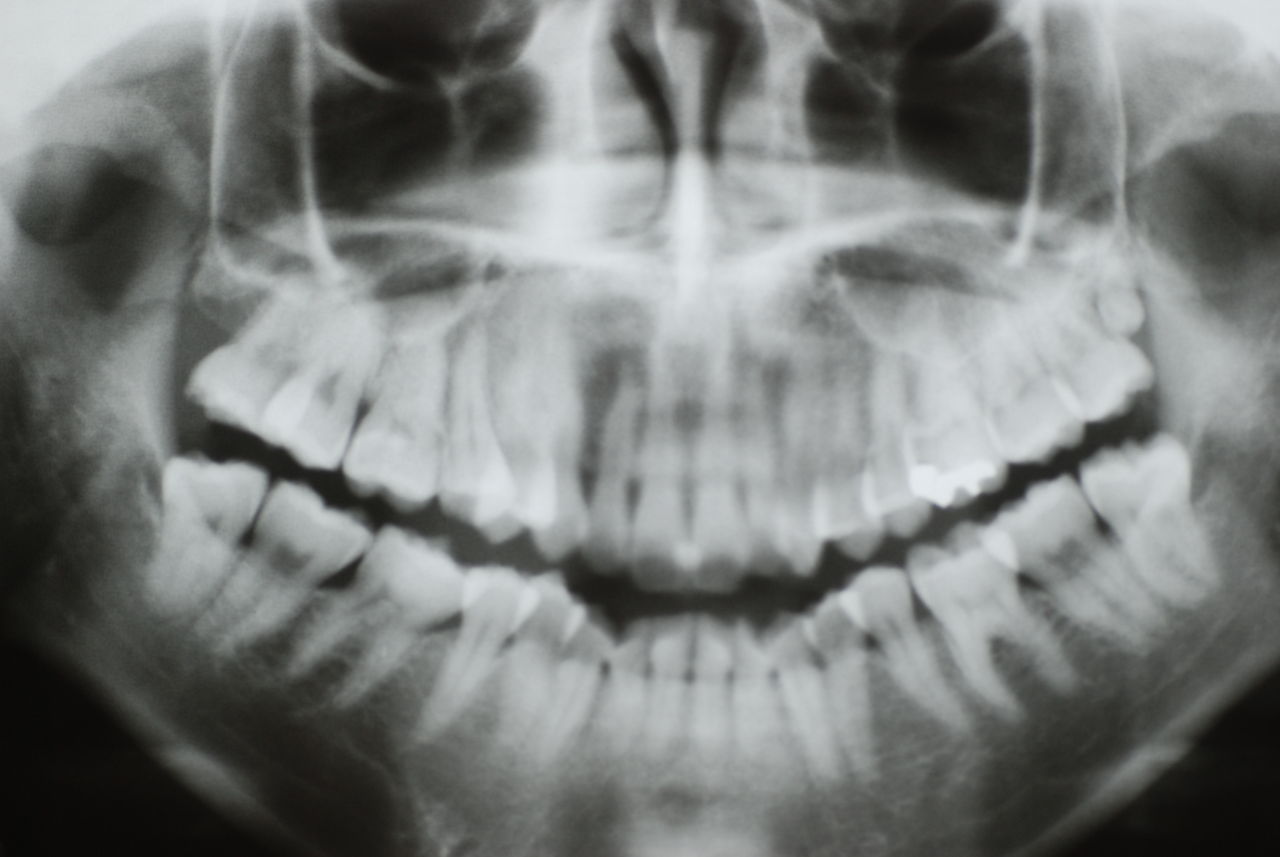

下記は患者に言われるままに血だらけでの不潔な状態で虫歯をとり埋めたようで全然適合していませんし、外れそうになっていました。

外したところです。中は虫歯のオンパレードでした。

適合が悪い銀歯が装着されていて更に虫歯の取残しにより歯髄炎症を起こして神経を取らざるをえなくなりました。神経を除去すれば痛みはなくなります。でもそれは死ぬことなのです。ほぼ寿命は半減したと考えるしかないのです。

まずは掃除の仕方を学ぶべきだったのです。環境をある程度良くしてから治療しないのでほぼ失敗に終わり、またハズレて虫歯により崩壊してしまうのです。